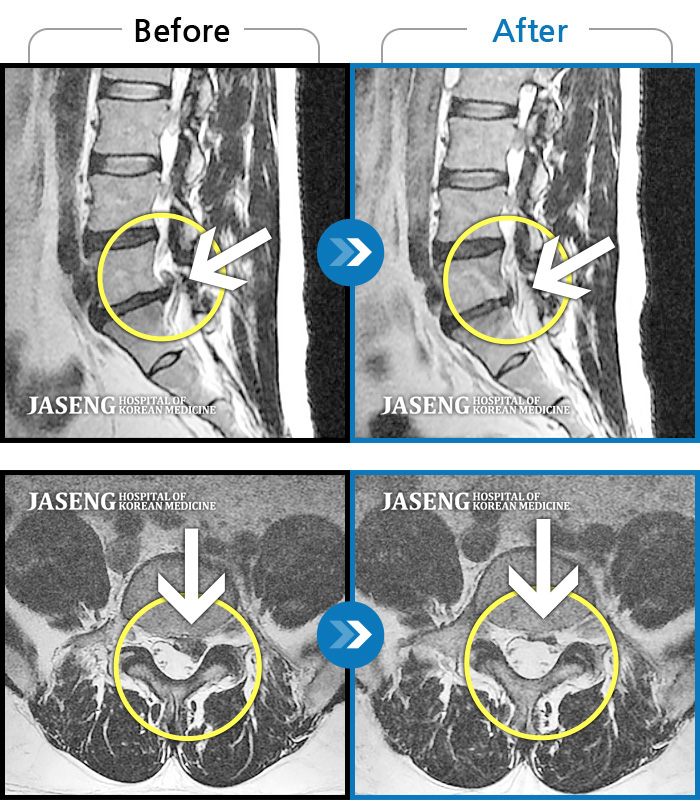

허리디스크

도움받은 사례

일산 · 김진수 원장

처음 내원 시 좌측 엉덩이가 많이 아프고, 좌측 다리로 저림이 심하며 특히 좌위시 하지 방사통이 심하여 1분도 좌위가 어려워 식사도 서서 하는 등 정상적인 활동이 힘든 상태였습니다.

촬영시기

2021.11.12 ~ 2024.07.23

2024.11.08